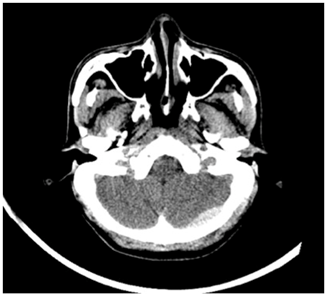

This led to the formulation of our criteria for PFEDH management, as shown below (Table 2). All bleeds greater than 4cms in horizontal diameter were taken up for surgery (Figure 6). For bleeds smaller than 4cms, GCS was employed as the deciding criterion, where patient with low GCS despite small bleeds were taken up for decompression and hematoma evacuation, while better GCS patients were observed (Figure 7).

Figure 7 Small posterior fossa extradural bleed, Conservative group.